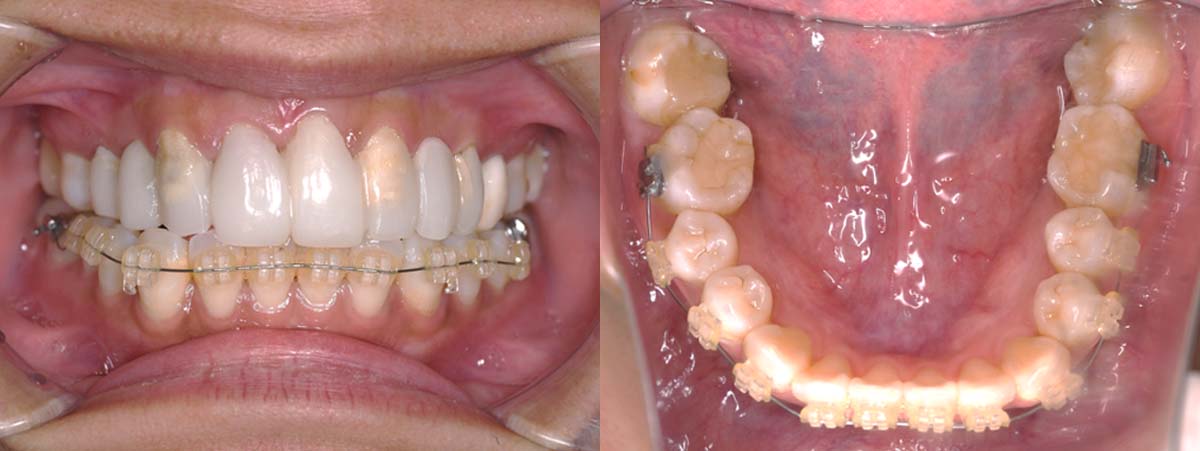

| 治療内容 | ①スプリントを装着 ②副子を装着 ③2024年4月 口腔内反映開始 ④副子を入れた状態の所まで咬合を挙上 (バイトアップ) ⑤2024年5月 上顎前歯部8本に仮歯(TEK) を装着 |

バイトアップ後

2024年 10月 下顎MTM開始